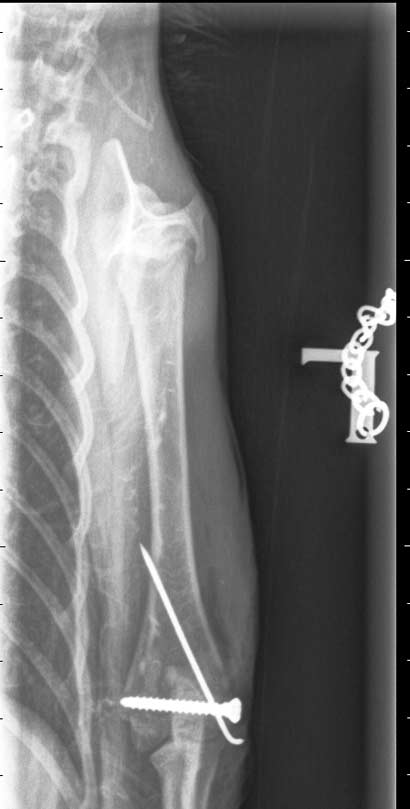

Looping war bei der Röntgenkontrolle

Der kleine Looping war in der Tierklinik zur Röntgenkontrolle und dabei wurden auch gleich die Fäden gezogen.

Seine Frakturen heilen gut zusammen - was bei jungen Tieren ja glücklicherweise rascher geht - und Looping darf bereits in zwei Wochen schon wieder mit Artgenossen springen und rennen.

Da er noch total verspielt ist und es gar nicht erwarten kann, mit anderen Katzen zu toben, freuen wir uns natürlich für ihn, wenn diese "Schonfrist" bald vorüber ist.